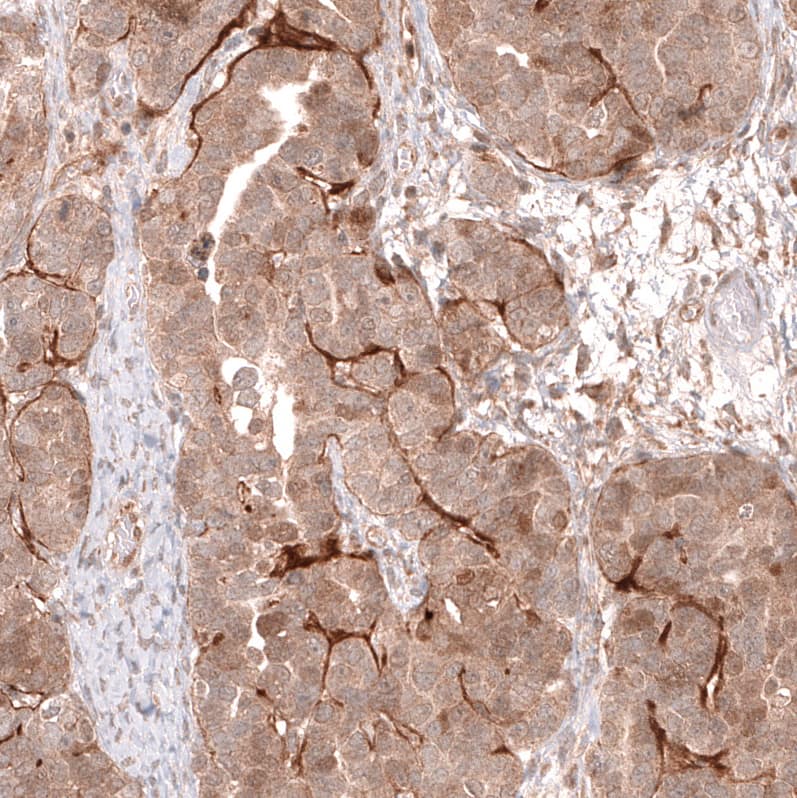

Staining of human colorectal cancer shows moderate cytoplasmic positivity in tumor cells.